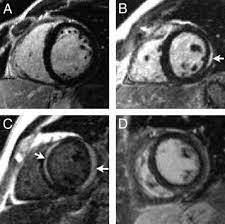

Inflammatory Episodes Of Desmoplakin Cardiomyopathy Masquerading As Myocarditis Unique Features On Cardiac Magnetic Resonance Imaging Jacc Cardiovascular Imaging

Inflammatory Episodes Of Desmoplakin Cardiomyopathy Masquerading As Myocarditis Unique Features On Cardiac Magnetic Resonance Imaging Jacc Cardiovascular Imaging from www.jacc.org